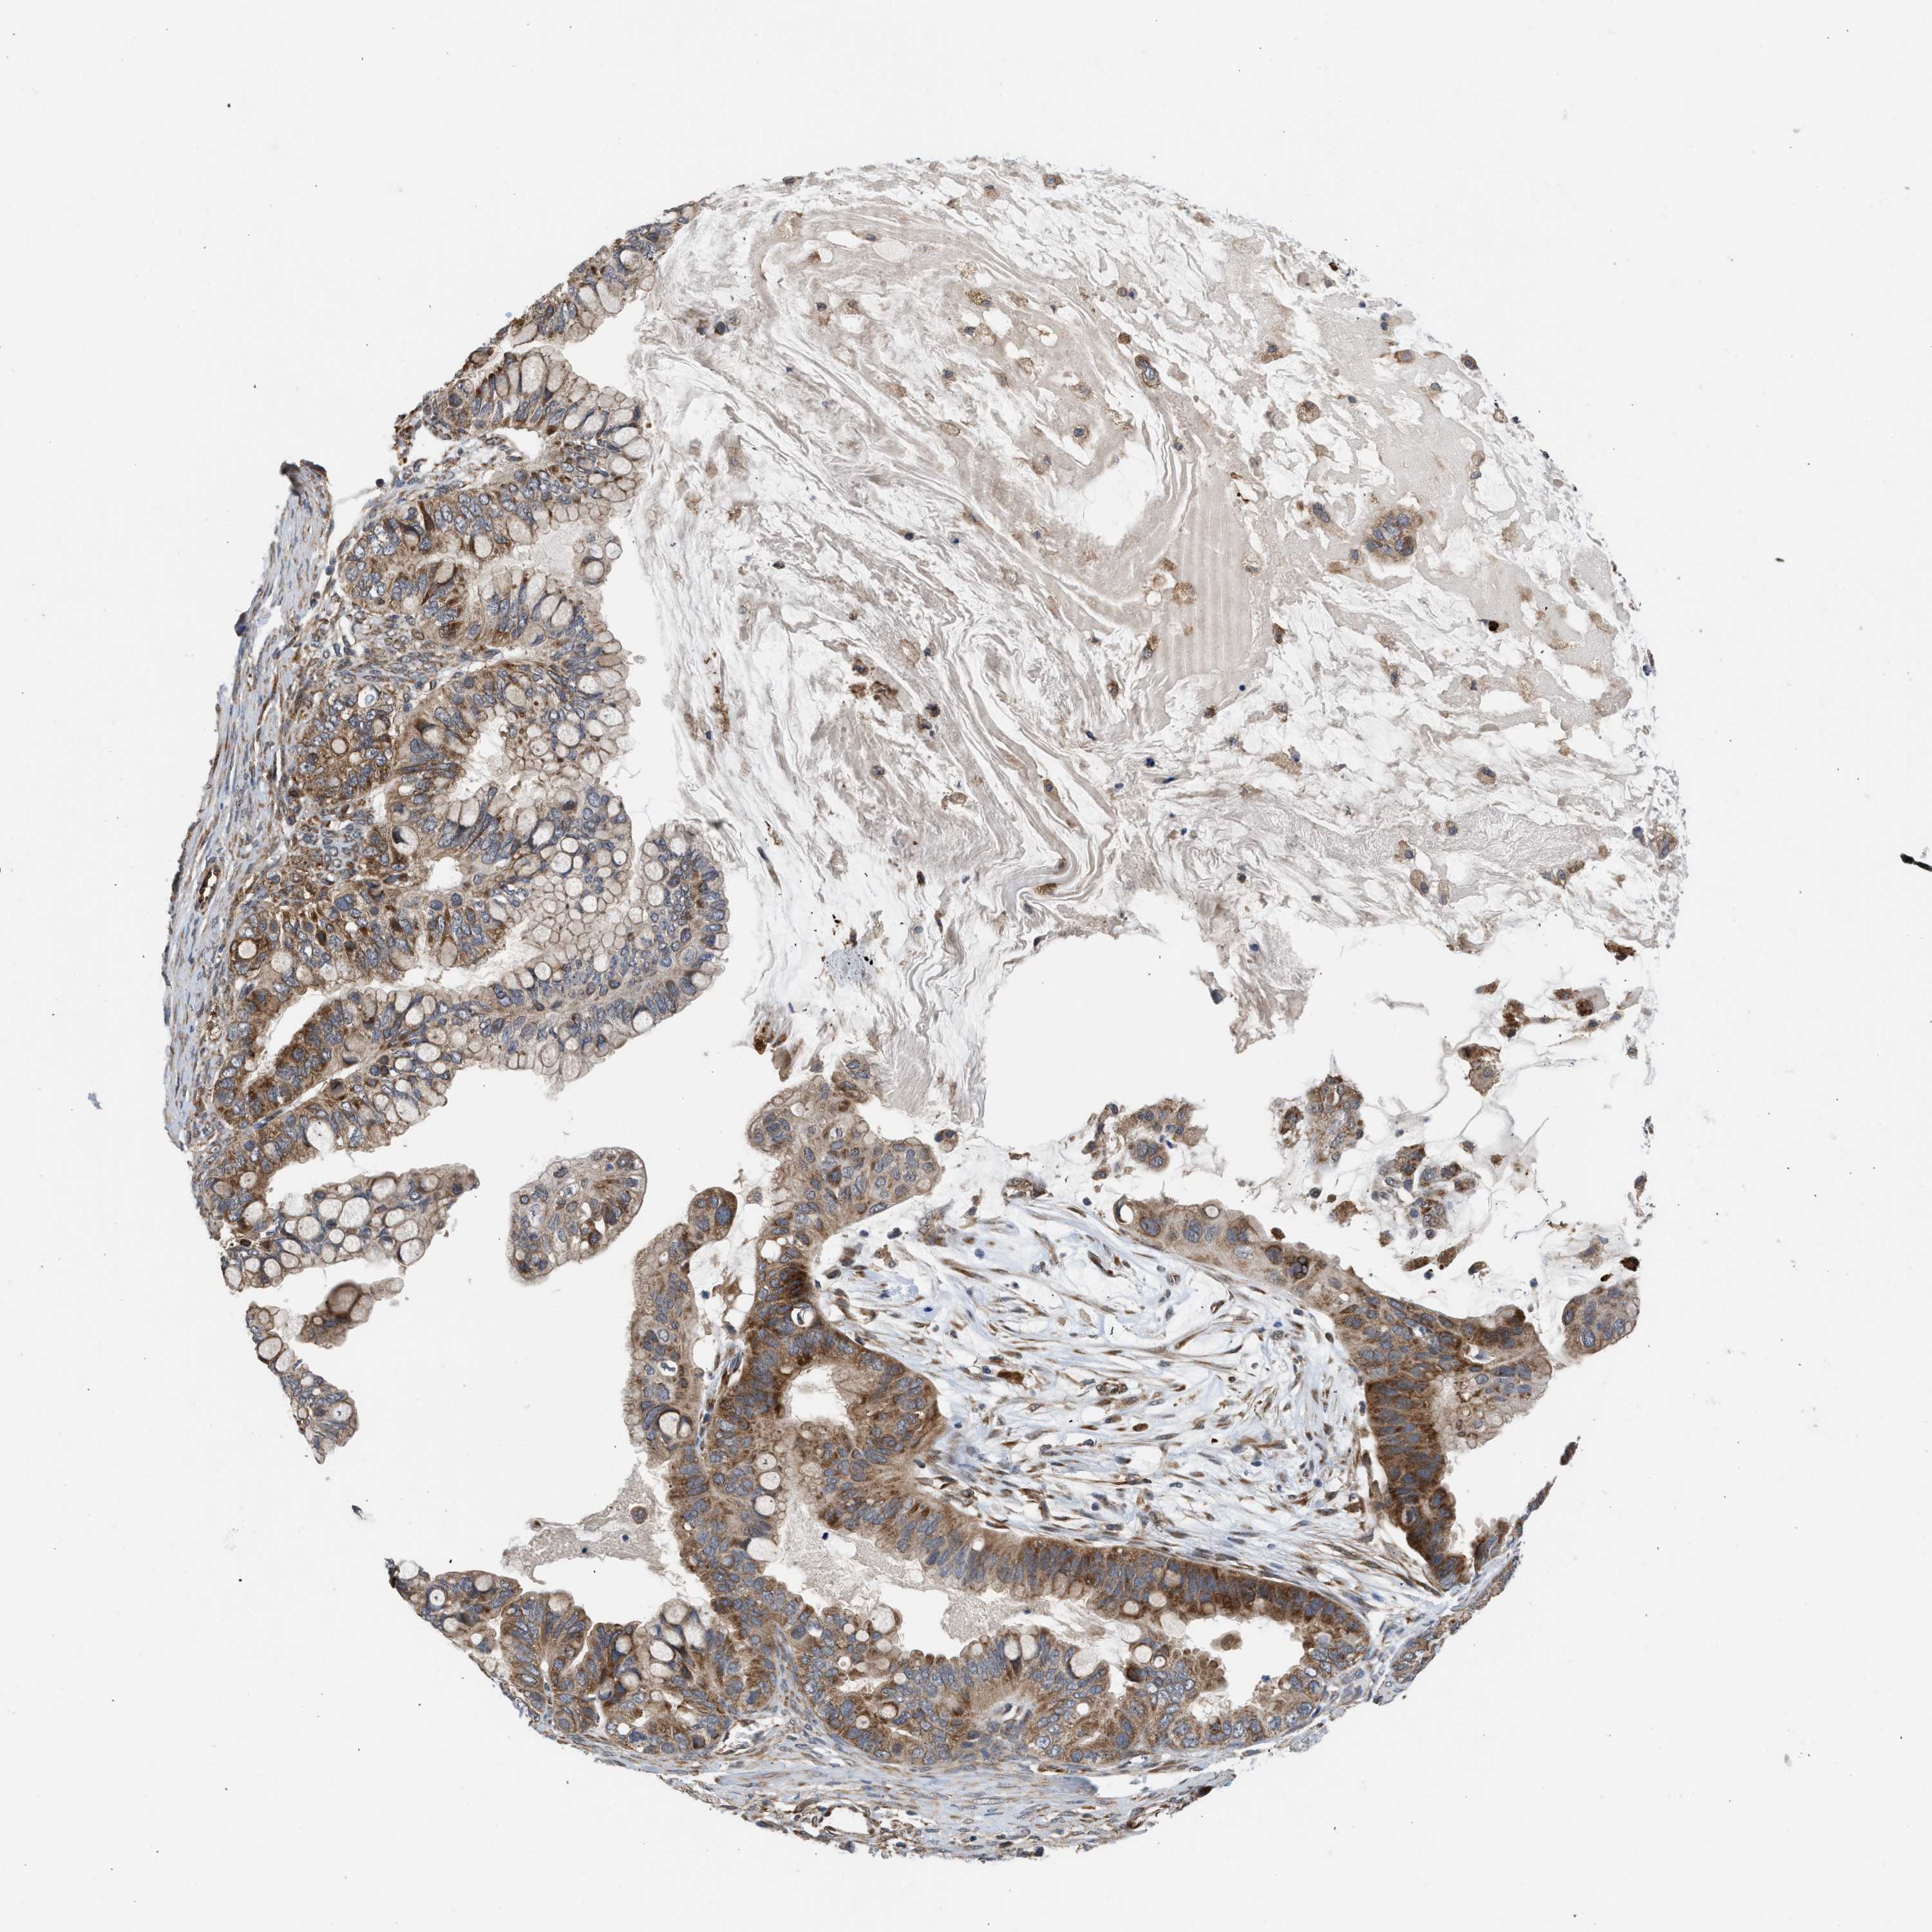

OVARIAN CANCER - Protein expressioni

A mouse-over function shows sample information and annotation data. Click on an image to view it in a full screen mode. Samples can be filtered based on level of antibody staining by selecting one or several of the following categories: high, medium, low and not detected. The assay and annotation is described here.

Note that samples used for immunohistochemistry by the Human Protein Atlas do not correspond to samples in the TCGA dataset.

Antibody stainingi

Antibody staining in the annotated cell types in the current human tissue is reported as not detected, low, medium, or high, based on conventional immunohistochemistry profiling in selected tissues. This score is based on the combination of the staining intensity and fraction of stained cells.

Each image is clickable and will lead to virtual microscopy that enables deeper exploration of all samples and also displays staining intensity scores, fraction scores and subcellular localization as well as patient and tissue information for each sample.

Antibody CAB017030